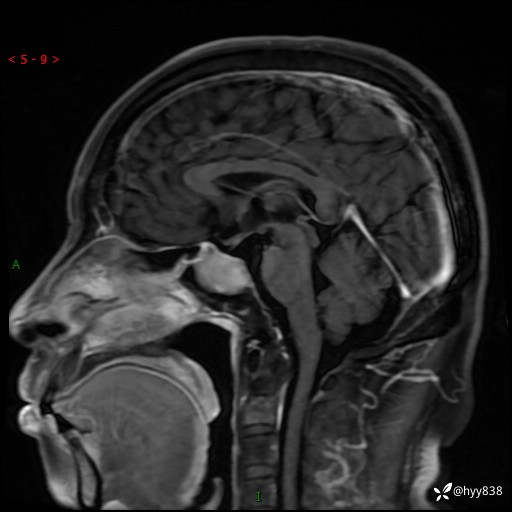

MRI增强(外院平扫)